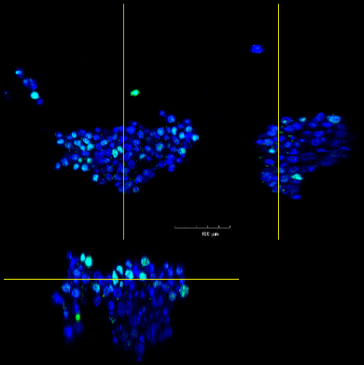

F-PDO®の3D解析

3D解析を用いた形態解析

青…DAPI(核を染色)

赤…actin(細胞骨格を染色)

緑…ZO-1(タイトジャンクションを染色)

【3D動画RLUN14】

【3D動画RLUN20】

3D解析を用いた形態的定量解析

- 青…DAPI(核を染色)

緑…Ki67(増殖細胞のマーカ) - 形態情報(細胞数、容積、Ki67陽性細胞数)を算出

- 細胞塊あたりの細胞数、細胞密度、増殖細胞の比率が算出することができる。

- F-PDO®の種類により、細胞塊の大きさ、細胞密度、増殖細胞の比率はさまざまである。